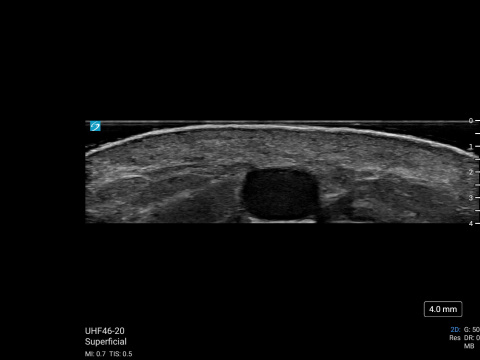

MSK Market Development Director, Daniel Shelton, shows off the capability of Sonosite UHF 46-20 with scans of a hair follicle and a vein. The scans were then illustrated to reveal details less obvious to the non-clinical eye.

Hair follicle on the back of a child's calf